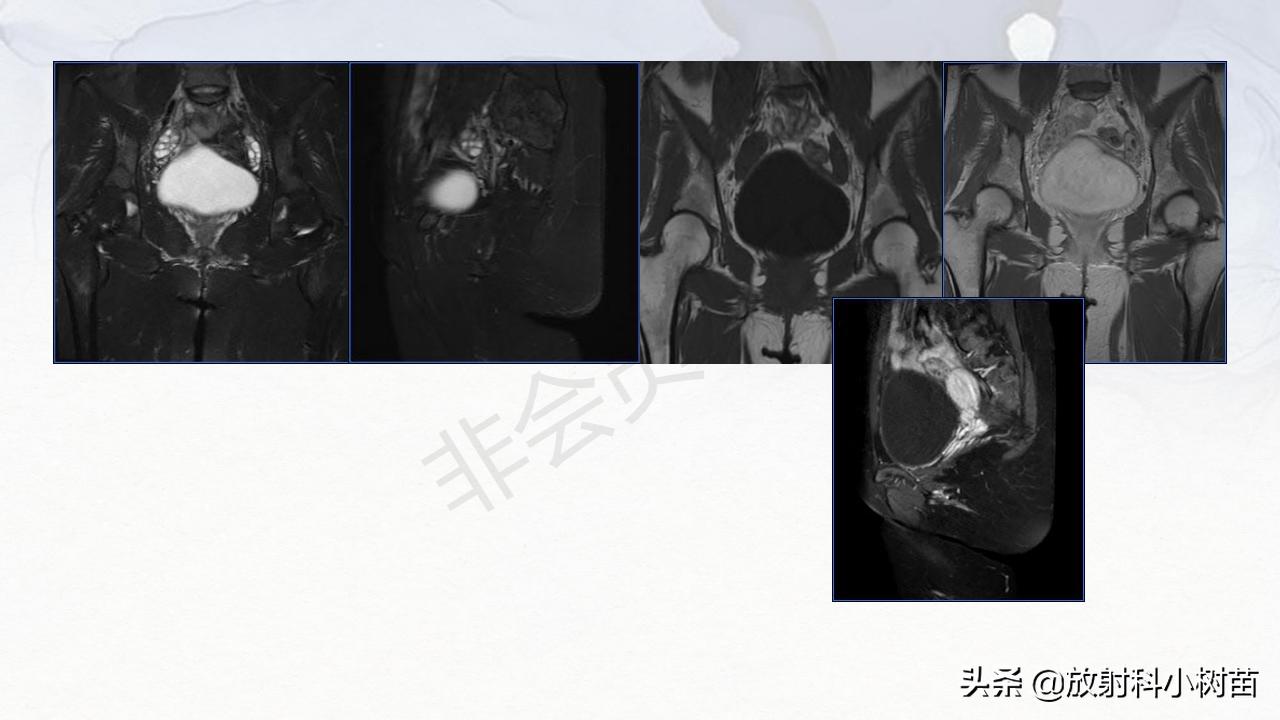

卵泡膜细胞瘤-纤维组肿瘤 :卵泡膜纤维瘤,纤维卵泡膜细胞瘤,卵泡膜细胞瘤,纤维瘤;是卵巢常见良性、实性肿瘤,但可囊变,并发胸、腹水,即麦格氏综合征。多见于绝经后妇女,良性肿瘤,可产生雌激素

卵巢:囊性?(单囊?(生理性囊肿,浆液性囊腺瘤、巧克力囊肿),多囊?(囊腺瘤,囊腺癌,巧克力囊肿),囊实性?(黏液性囊腺瘤,囊腺癌,癌畸癌),实性?